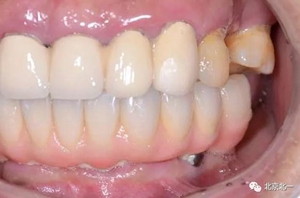

圖二十四:2017年11月復(fù)查時(shí)照片,植體很穩(wěn)定, 無骨吸收。

圖二十五:口內(nèi)照。